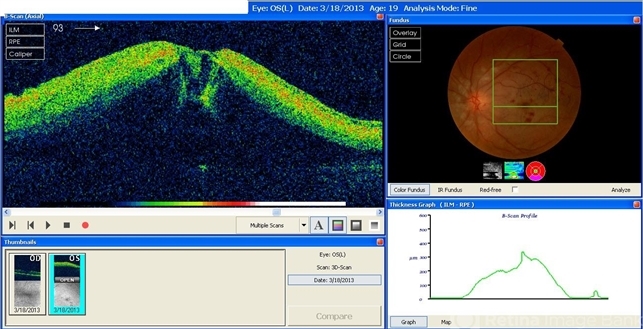

- A 20-year-old male suffered from diplopia since age one. He was diagnosed to have acquired fourth nerve palsy in his left eye. VA at time of diagnosis was 20/20 in OU and fundus exam was WNL in OU. His history reaveled no other complaints. 3 days ago he underwent left superior oblique tucking for relief of his diplopia.The surgery was uneventful and at the end of surgery subconjunctival gentamicin was injected. Immediately following surgery his VA in OS decreased from 20/20 to complete loss of central vision and sensation of HM from the periphery. He was referred to us 3 days after surgery. At time of referral fundus exam of his left eye revealed macular infarction with cherry red spot appearance with few retinal hemorrhages , mild optic disc edema and CWS surrounding optic disc. Peripheral retina had normal color and appearance. The vitreous was clear. Anterior segment was quiet. IOP was WNL. Macular OCT was consistent with macular infarction. FA revealed delay in central retinal artery filling as fluorescein started to appear in the arteries at the level of the optic disc at 28 sec, and in the retinal veins at 38 sec. Macular area remained to be non-perfused throughout the whole FA. In late phases staining of blood vessels walls was noticed. The "wipe out" of large vessels and capillaries persisted in the central area. OCT through foveal area showed diffuse thickening of the retina with severe elevation in the fovea, reduced backscattering from the outer layers of the retina and enhanced reflectivity from the inner retina, due to ischemia. Complete blood count and cardiovascular study were WNL. The final diagnosis was macular infarction secondary to subconjunctival gentamicin injection.